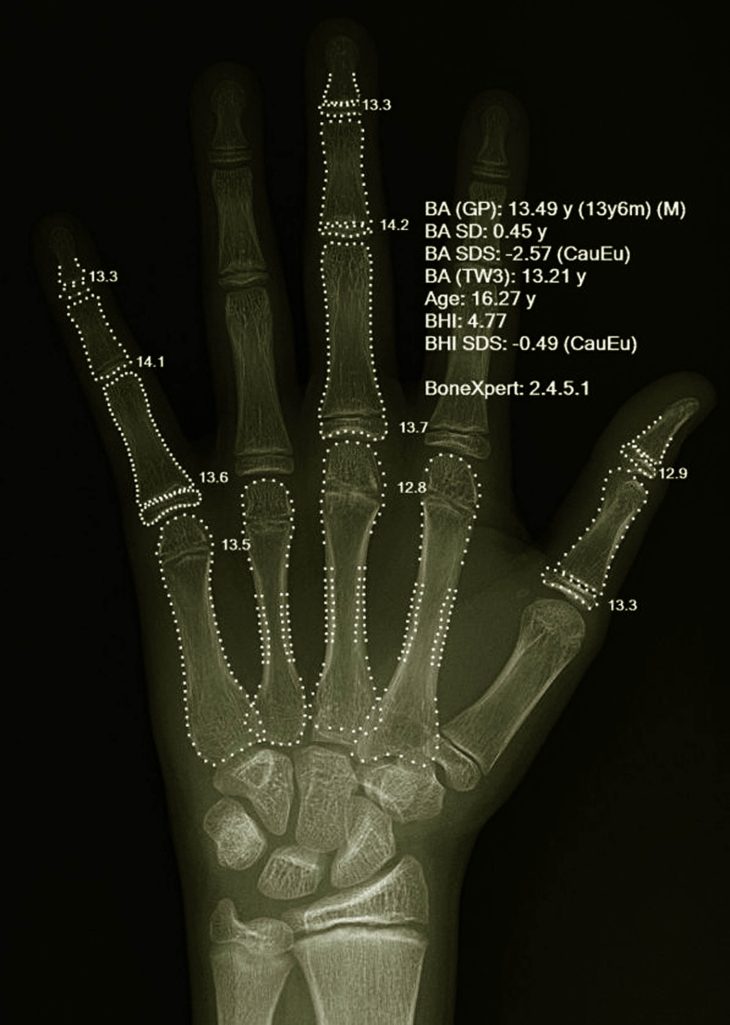

Las tres variables son normales dado que dentro del crecimiento hay que considerar las medidas físicas o antropométricas y la maduración biológica, la cual se determina mediante la edad ósea, que se establece con base en una radiografía de muñeca y huesos de la mano izquierda (carpo) para comparar los puntajes de conformidad a las normas internacionales, abundó la antropóloga Sáenz Faulhaber.